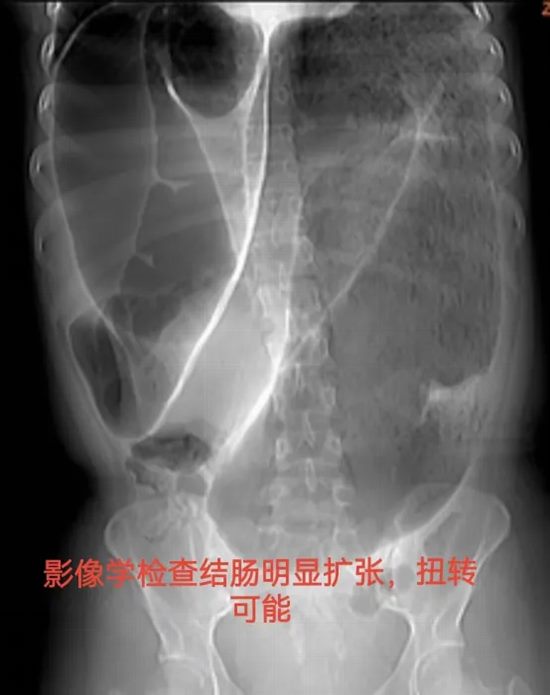

病例十:花季少女腹痛四年,竟是结肠“长错了”?

病情简述:19岁女性,间断腹痛腹胀4年,辗转求医未果。此次因急性加重急诊入院。

诊疗破局:CT提示结肠梗阻,非手术减压无效。急诊剖腹探查发现元凶是罕见的“结肠重复畸形”并扭转。及时的手术不仅解除了急性梗阻,切除了病变肠段,更找到了困扰她4年的病根。术后患者恢复良好,已回归正常生活。

技术体现:面对罕见急腹症,果断的手术决策与扎实的探查功底,是挽救患者、明确病因的根本。